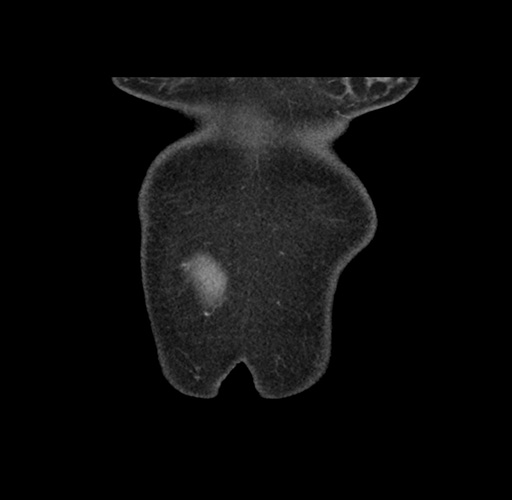

Imaging Analysis

Look through the patient's CT scan to identify any areas of concern for the necessary procedure.

Based on your CT findings, which issue(s) would give reason for "planned slowing down moment(s)" in this case?